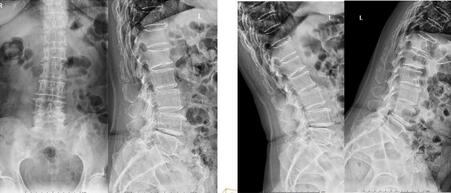

手術(shù)方案:全麻下行“腰椎間盤摘除+腰椎管減壓植骨融合內(nèi)固定術(shù)”。取腰背部后正中縱行入路;骨膜下剝離椎旁肌,椎管減壓、植入椎弓根螺釘,保護(hù)脊髓及神經(jīng)根,摘除髓核,搔刮終板、椎間植骨并安置融合器;抱緊、安裝椎弓根螺釘、棒系統(tǒng);嚴(yán)密止血、放置引流、關(guān)閉切口。

術(shù)后恢復(fù):整個(gè)手術(shù)過程順利,術(shù)畢病人安返病房,術(shù)后給予抗炎、止血、消腫、止痛、抑酸等對癥處理。